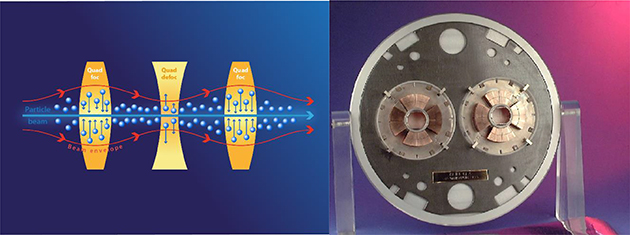

Low-energy electrons have historically been used to treat cancer for more than five decades, but mostly for the treatment of superficial tumours given their very limited penetration depth. However, this limitation can be overcome if the electron energy is increased between 50 and 200 MeV (i.e., very high-energy electrons, VHEE; figure 5.1). With the recent developments of high-gradient normal conducting (NC) radio frequency (RF) linac technology (figure 5.2) (CLIC Project n.d.) or even the novel acceleration techniques such as the laser-plasma accelerator (LPA) (figure 5.3), VHEE offer a very promising option for anticancer RT. Theoretically, VHEE beams offers several benefits. The ballistic and dosimetry properties of VHEE provide small-diameter beams that could be scanned and focused easily, enabling finer resolution for intensity-modulated treatments than is possible with photons beams. Electron accelerators are more compact and cheaper than proton therapy accelerators. Finally, VHEE beams can be operated at very high-dose rates and fast electromagnetic scanning providing uniform dose distribution throughout the target and allowing for unforeseen RT modalities in particular the FLASH-RT.

From the accelerator technology point of view the major challenge for VHEE-RT is the demonstration of a suitable high-gradient acceleration system, whether conventional, such a X-band or not, with the stability, reliability, and repeatability required to be operated in a medical environment. In particular, for the VHEE-FLASH is the delivery of very high dose rate, possibly over a large area, providing uniform dose distribution throughout the target (Faus-Golfe 2020).

To enhance the coverage of particle therapy in Europe and worldwide and to enlarge the number of patients that can profit from this special treatment, the investment costs of such facilities should be reduced as much as possible, which requires smaller and simpler machines to reduce manufacturing and operating effort. Especially the size of the accelerator has an important influence on the building costs. And the amount of beam losses demands more or less concrete for radiation shielding, and should be minimized by design. In addition, the operating and maintenance team needed should be small, but adequate and well-trained, and sustained by a modern control system, which predicts pre-emptive maintenance measures through AI algorithms and thus guarantees highest availability.

Towards a VHEE RT facility

NC RF linac is the technology being used for most of the VHEE research. The main advantages of the linacs are the flexibility and the compactness. Regarding the linac design in the energy range of interest for VHEE applications there are different possibilities offering the desired performances and compactness with different degrees of technology maturity. The S-band technology is the most mature one; HG compact linacs of this type are already available from various industrial partners. The C-band and X-band RF linacs are still less mature and are mainly constructed in labs with the help of industries for machining. Recently a considerable effort is being made from the industrialization point of view. The current and next future available machines for VHEE are the eRT6-Oriatron at Centre Hospitalier Universitaire Vaudois in Laussane; ElectronFlash at IC in Orsay; CLARA at Daresbury; AWA at ANL; and CLEAR at CERN (all based on NC RF linacs). A VHEE-FLASH facility based on a CLIC X-band 100 MeV linac is being designed in collaboration with CHUV to treat large, deep-seated tumours in FLASH conditions. The facility is compact enough to fit on a typical hospital campus (figure 5.5). Another proposal in this sense is the upgraded PHASER proposal at SLAC. Finally, ELBE at HZDR and the next future PITZ at DESY are based on SCRF linac technology.

Standard image High-resolution imageRecent advances in the high-gradient RF structures where more than 100 MeV m−1 are now achievable in the lab environment are transforming the landscape for VHEE RT. VHEE RT requires beam energies between 50 and 200 MeV, an improved dose conformity and scale to higher doses rates, in the case of the FLASH-RT until 50 Gy s−1 are needed. Novel high-gradient technologies could enable ultra-compact structures, with higher repetition rates and higher currents. An international R&D global effort is being made by major accelerator laboratories and industry partners and is focused on two aspects: material origin and purity, surface treatments, and manufacturing technology on the one hand and the consistency and reproducibility of the test results on the other. Some promising R&D in the next decade are the distributed coupling accelerator developed at SLAC and the use of cryogenic copper that is transforming the linac design offering a new frontier from beam brightness, efficiency, and cost capability. Another approach for the next generation of compact, efficient, and high-performance VHEE accelerator is the use of higher-frequency millimetric waves (∼100 GHz) and higher repetition rates using THz sources.